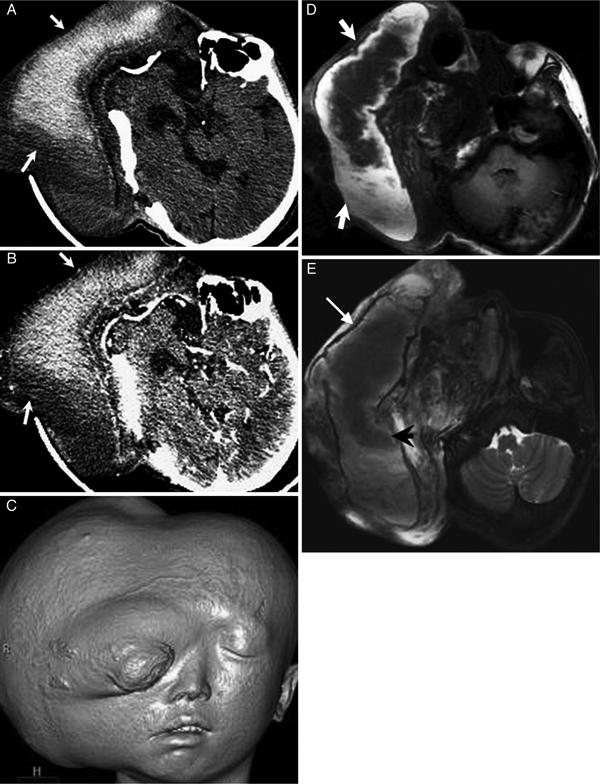

头面部巨大丛状神经纤维瘤伴出血的 CT 和 MRI 表现。

Giant plexiform neurofibroma with hemorrhage in cranio-maxillofacial region as depicted on CT and MRI.

Plexiform neurofibroma (PN) is a rare benign tumor and a special subtype of neurofibromatosis type 1 (NF1). Though the incidence is low, giant PN of the craniomaxillofacial region could result in severe hemifacial hypertrophy which is known as a typical manifestation of NF1 in young children. Here, we retrospectively reported a giant plexiform neurofibroma with hemorrhage in the cranio-maxillofacial region detected by CT and MRI. In addition, a brief review of the relevant literature is presented.

摘要

丛状神经纤维瘤(PN)是一种罕见的良性肿瘤,也是神经纤维瘤病 1 型(NF1)的特殊亚型。尽管发病率较低,但发生于颅颌面区域的巨大丛状神经纤维瘤可导致严重的半侧面部肥大,这是 NF1 在幼儿中的一个典型表现。在此,我们回顾性报告了一例 CT 和 MRI 检查发现的颅颌面区域巨大丛状神经纤维瘤伴出血病例,并对相关文献进行了简要复习。